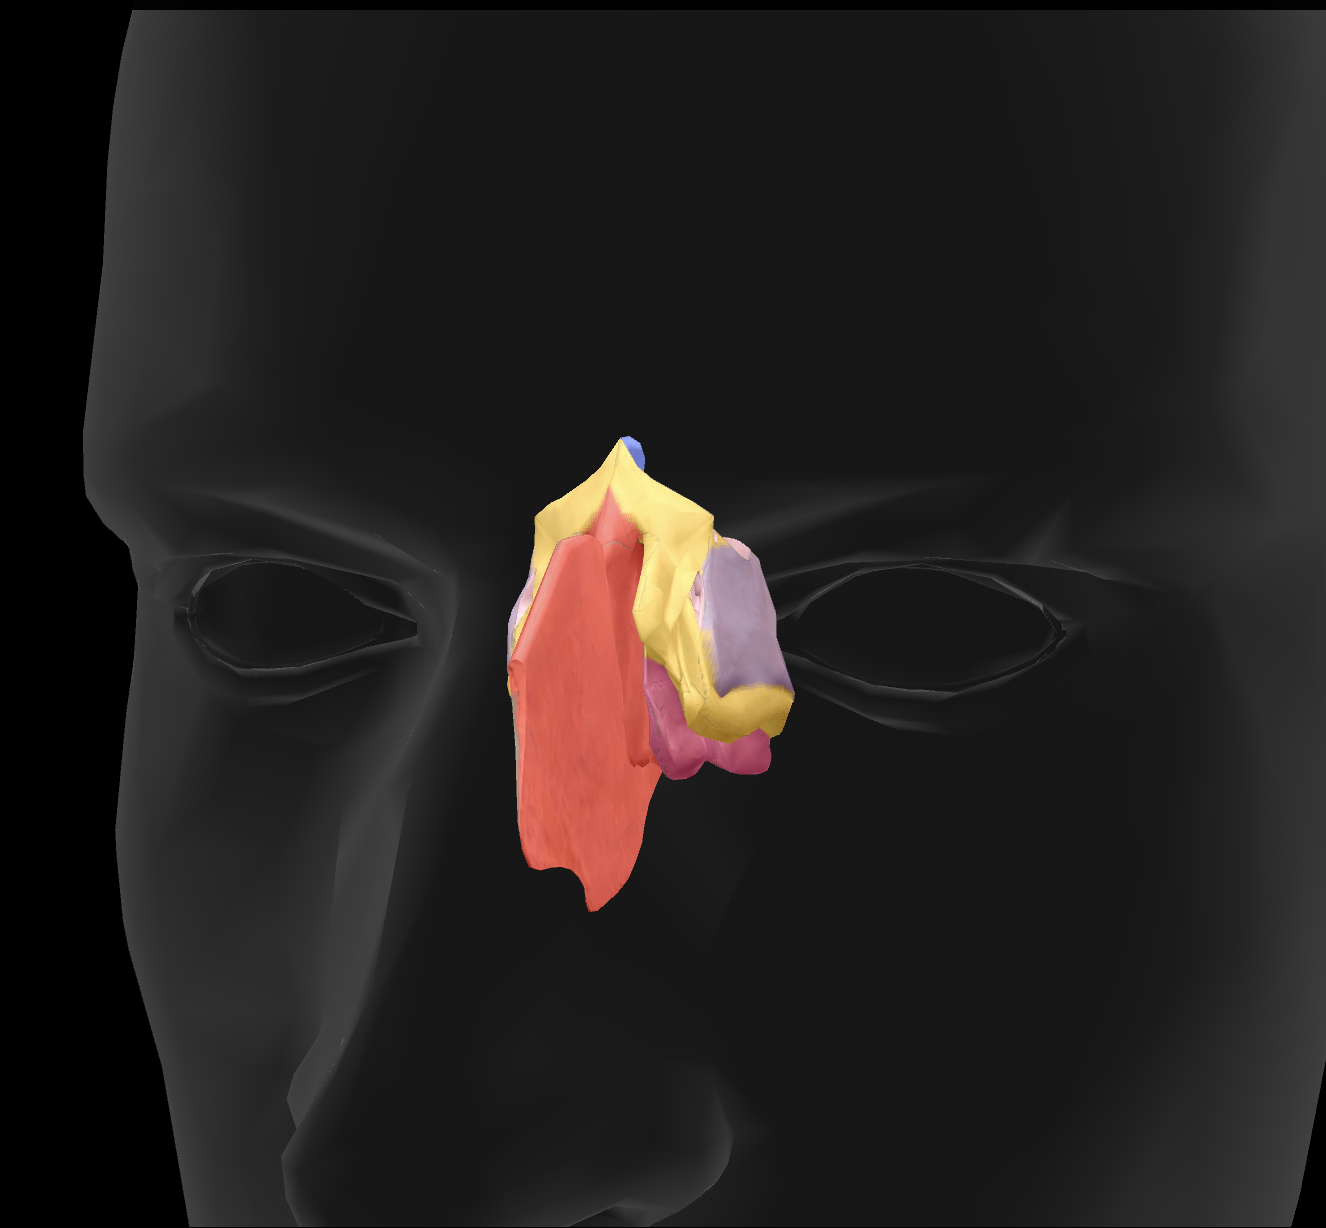

What features make up the nasal septum?

perpendicular plate of ethmoid bone and vomer

What is the name of this feature?

perpendicular plate

What is the name of this feature?

middle nasal conchae

What is the name of this feature?

superior nasal conchae